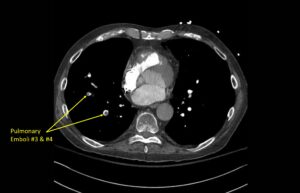

Wolff A, et al. Right atrial thrombosis. CT axial, PE 3

Wolff A et al. Right atrial thrombosis. CT axial PE 3